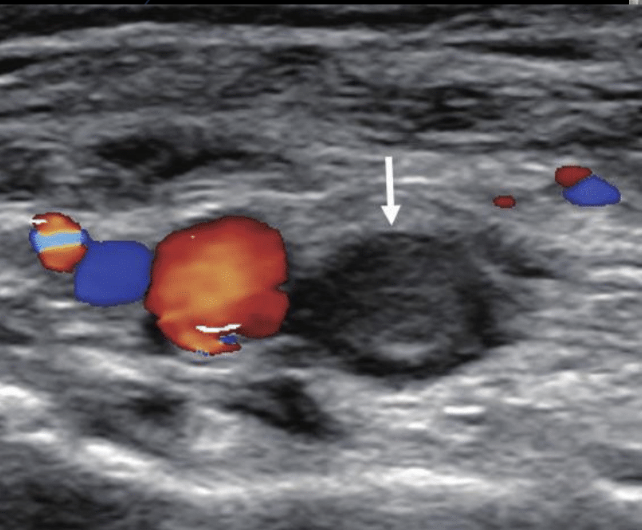

Qué ves?

Trombosis venosa